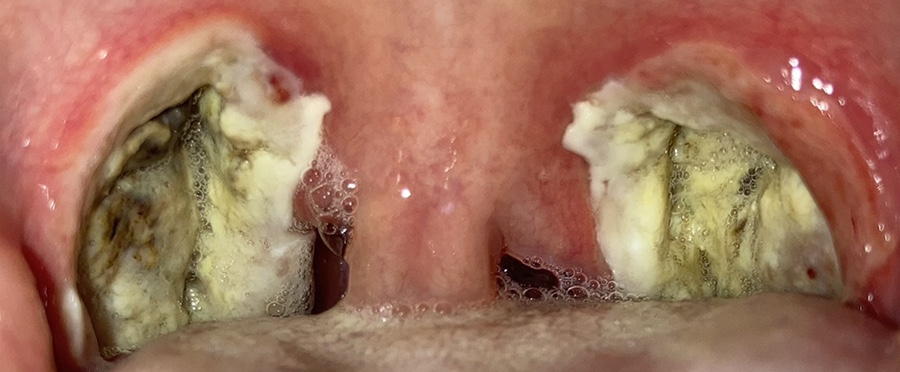

이건 수술 후 사진을 찍은 거야.

목젖은 가라앉았지만 전기로 부서졌다는데 사흘째가 되자 딱지가 심해졌다. 사진은 셋째 날과 넷째 날이 같았기 때문에 넷째 날은 찍지 않았다.

5일째가 되자 딱지가 붙었다. 목젖도 아직 부은 것 같아. 그리고 목이 너무 아파 아직 옆으로 자야해. 그리고 목이 부어서 그런지 내가 잘 때 “이~~~~~~~~~~~~~~~~~~~~~~~~~~~~~~~~~~~~~~~~~~ 인터넷을 검색해보니 수면장애였다. 목이 이렇게 부어 있는데 안 날 리가 있나 보군.